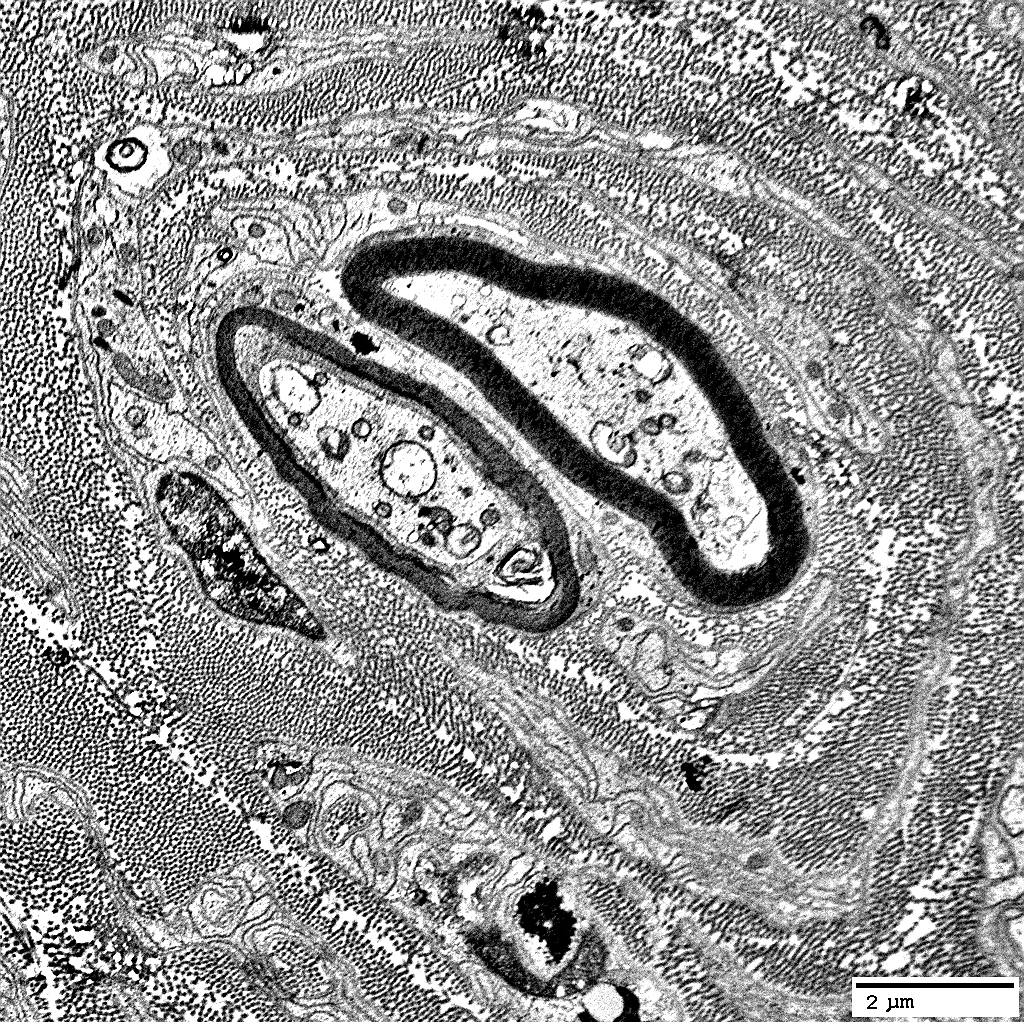

Onion Bulbs

Some contain myelinated axons; Others are empty (

"Obsolete")

Myelin sheaths: Thick; Normal or Thin

Contain abundant

non-myelinating Schwann cells